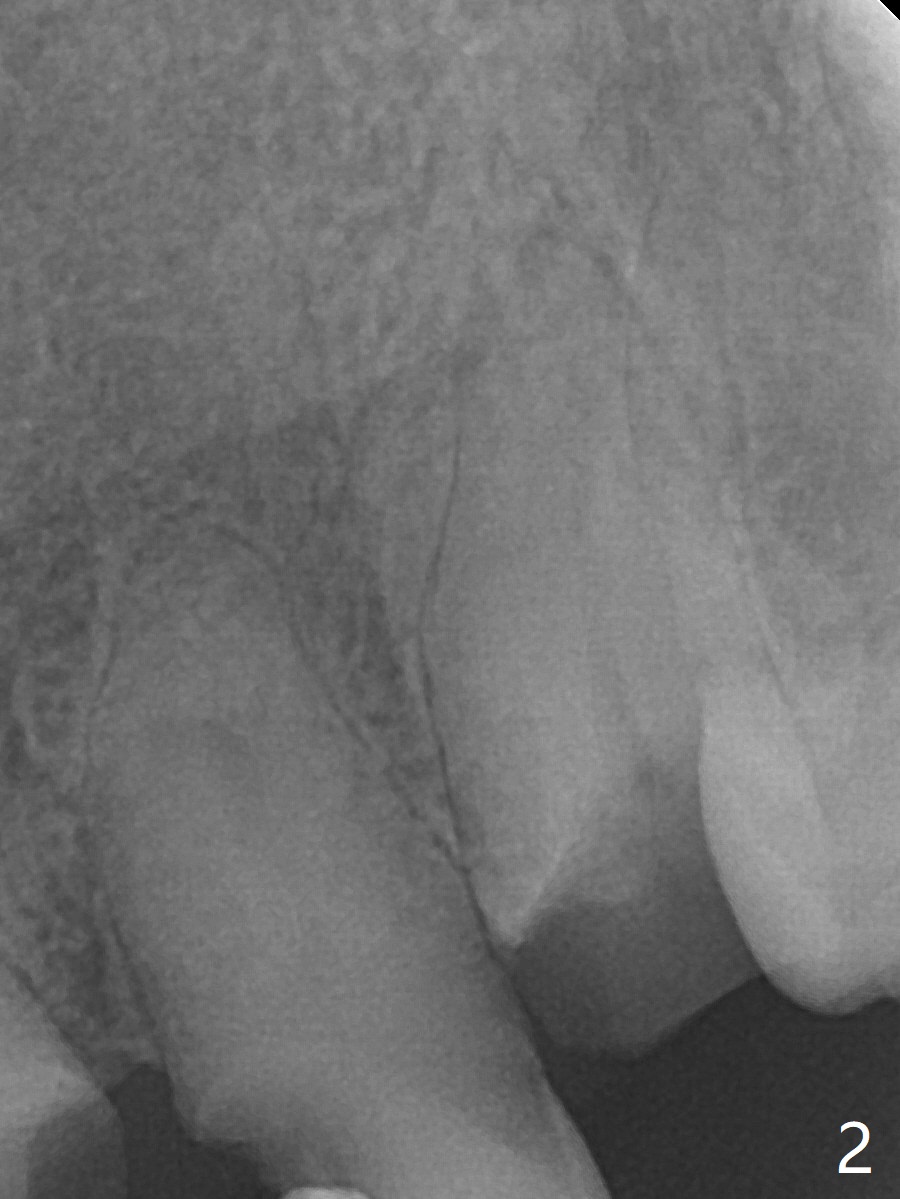

64岁男要求拔除左上3(图一,二),将使用Piezo P3 tip(图三)松动牙根,可行?其实图三是G6,used for removal of calculus from a wide plane. G:可能代表general use or general dentistry,而P牙周(图四)。P3(买了好久,不知道用处)特别细长,容易进入牙周膜,但愿在小功率的普通Piezo Scaler (超声洁牙机)作用下,P3能切断牙周膜,午饭后尝试。其实尖牙无症状(图五),中切牙(在侧切牙位置上)因近中深龋造成牙龈炎症,在病人要求下,清除龋坏后,填入临时充填物(图五,六)。